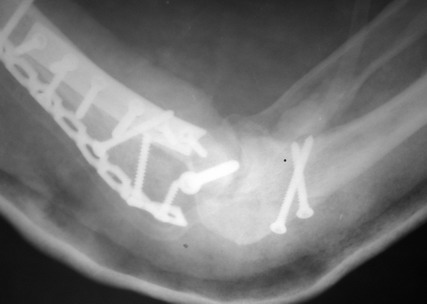

Солидарен с мнением обоих Александров (Челнокова и Рыкова): точную репозицию такого перелома вряд ли удастся выполнить закрыто. Даже во время открытого вмешательства это сделать непросто. Неслучайно предложен костно-пластический доступ с временным отсечением локтевого отростка. И по методу фиксации согласен с Александром Челноковым: 2 пластины. В качестве примера привожу рентгенограммы одного из наших пациентов с аналогичным повреждением.

С уважением, А. Золотов, Приморский край.

Примерный случай, только перелом был открытый, в задне-медиальной стороне рана около 2 см по характеру "изнутри кнаружи", неврологический статус со слабостью сгибания мизинца, также слабая абдукция и аддукция указательного пальца и сгибания в кисти.

Больному сделали обработку и наложили временный аппарат внешной фиксации плечо-предплечье.

На шестой день сделали открытую репозицию чрезлоктевым доступом двумя locking plate, локтевой нерв был ушибленным, после операции положительная динамика в Flexor Carpi Ulnaris. Фиксацию локтевого отростка произвели tension band technique с дополнительным шурупом.

Этапы операции на снимках....